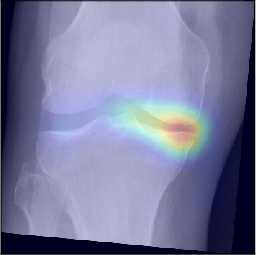

To gain insight into the basis of the CNN’s prediction, we used the GradCAM [24] approach and visualized the attention maps for the well-predicted knees. Examples of attention maps are presented in Figure 5. We observed that in various cases, the CNN paid attention to the compartment opposite to the one where degenerative change became visible during the follow-up visits. Additional examples of such attention maps are presented in Supplementary Figures 3, 4, 5 and 6.

Refer to caption

(a)

(b)

(c)

(d)

Figure 5: Examples of attention maps for progression cases and the corresponding visualization of progression derived using follow-up images from MOST datasets. Here, subplots (a) and (c) show the attention maps derived using a GradCAM approach. Subplots (b) and (d) show the joint-space areas from all the follow-up images (baseline to 84 months). Here, the subplot (b) corresponds to the attention map a) and the subplot (d) corresponds to the attention map (c).